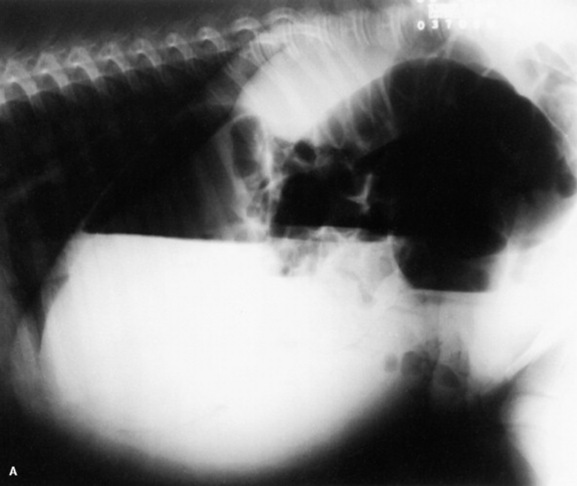

Skeletal maturity is assessed by radiographing a carpus and a tarsus for evidence of incomplete ossification (Fig. 19-1). Accelerated ossification does not appear to be a feature of foals born prematurely after exposure to chronic in utero stress. Incomplete ossification coupled with periarticular laxity predisposes the premature or dysmature foal to long-term skeletal problems. Foals with incomplete ossification and more than 30% reduction of the central and/or third tarsal bones with pinching or fragmentation of the dorsal aspects of affected bones commonly develop degenerative joint disease and have a guarded prognosis for future athletic performance. Restriction of exercise is recommended in order to minimize collapse of developing carpal or tarsal bones, but forced recumbency may predispose the foal to or exacerbate pulmonary disease. Furthermore, normal load bearing encourages ossification. Periarticular laxity predisposes the premature foal to angular limb deformities that facilitate abnormal load bearing and increase the risk of cuboidal bone crush injury of the carpus or hock. Splinting and attention to hoof care are recommended if angular limb deviation develops. In most cases flexural deformities and laxities improve over time. Dorsal splints are recommended for flexural deformities involving the fetlock, and heel extensions are helpful to foals with flexural laxity.

Fig. 19-1 A, Lateral tarsus of a 1-day-old, 305-day gestational age colt. Note the lack of ossification of the small tarsal bones. B, Lateral tarsus of the same foal as in A, at 3 weeks of age, showing irregular ossification. Without the initial radiograph, increasing ossification could have been confused with bone lysis and osteomyelitis. The foal is reported to be sound at 6 months of age.